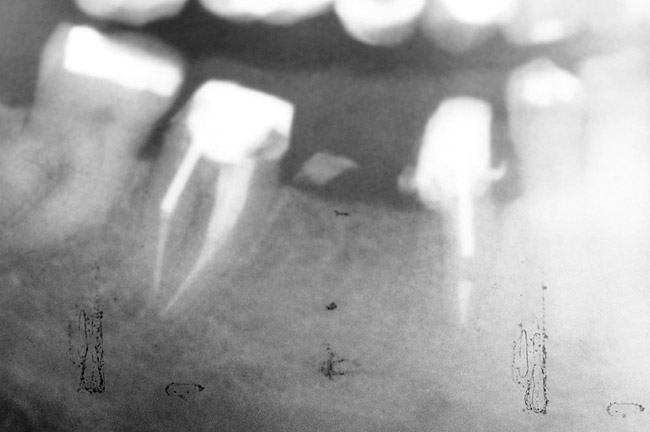

Figure 1  Tooth No. 5 showing advanced periodontal bone loss and a widened periodontal ligament space.

Figure 1

Figure 2  Same case as in Figure 1 after 1.5 years with no treatment. At that time, the bone loss affected the adjacent teeth. The apical extent of the bone loss was approximately 5 mm from the sinus floor.

Figure 2

Figure 3   Radiographic appearance of the repaired osseous defect seen in Figure 2 approximately 6 months after extraction and immediate bone grafting of the socket. Note the radiographic repair of the bone on teeth Nos. 4 and 6.

Figure 3

Figure 4  Clinical photograph showing preservation of the ridge seen in Figure 3.

Figure 4

To meet the needs of the new paradigm, treatment techniques have evolved for bone preservation. Figure 1 shows a case in which tooth No. 5 had advanced bone loss and the treatment option was to save it. The patient did not opt to have this treated, however. Figure 2 shows the same area approximately 18 months later when the advanced bone loss was also affecting the adjacent teeth. Traditional treatment—extraction of this tooth—would have led to a significant hard- and soft-tissue defect. Use of the alternative treatment—grafting of the socket at the time of extraction19,20—preserved the hard and soft tissue (Figure 3 and Figure 4). Grafting the socket to minimize postextraction ridge shrinkage is a much more conservative approach than performing ridge augmentation after extraction,21 which would have been required if the socket grafting had not been done in conjunction with the extraction.